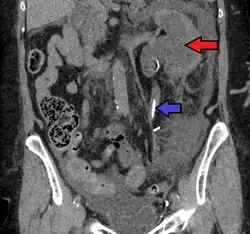

-

Peripelvic renal cysts may look like hydronephrosis on non-contrast CT (left image). However, CT urography (at right) reveals non-dilated calyces and pelvises.